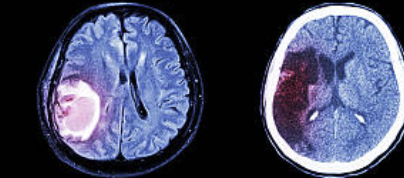

뇌경색은 뇌혈관이 막히면서 해당 부위에 혈류가 차단되어 뇌세포가 괴사되는 질환이며,

갑작스럽고 극심한 두통은 출혈성 뇌졸중에 흔하지만,

일부 허혈성 뇌경색에서도 초기 신호로 나타날 수 있습니다.